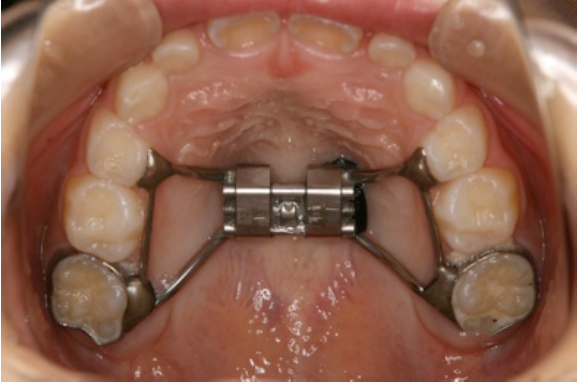

ステロイドを使用している子供の歯列弓は狭窄している。などなど・・。結論的にはこの上顎拡大装

置を使用すると非常に治療効果が高いようです。でもまあ「歯医者が喘息を治療する・・」なんて言

れることも度々です。そのほか、この上顎拡大装置を使って効果の

ある疾患は、小児のアトピー、おねしょ、睡眠障害(寝相の悪

さ)、いびき、難聴、花粉症などのアレルギーです。当然ですが歯

列不正も大きく改善されます。大人の身体になってから歯列矯正を